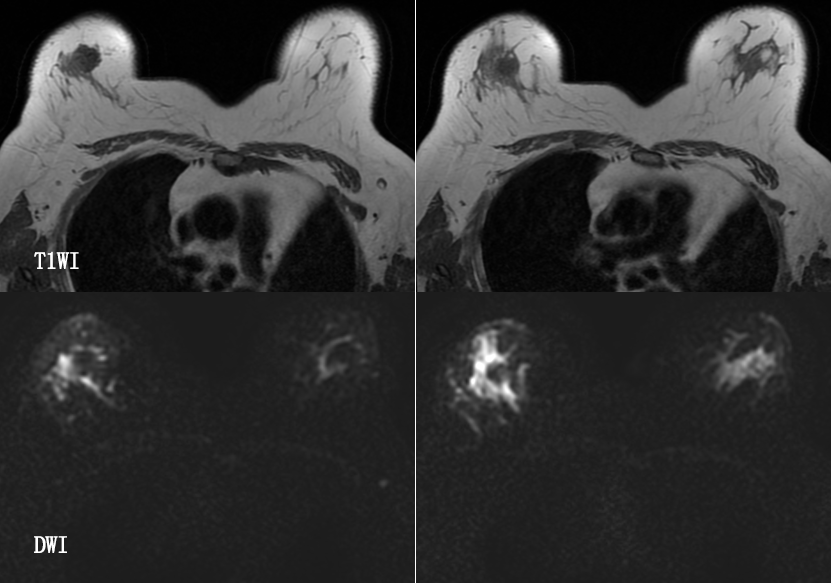

乳腺炎:包括急、慢性乳腺炎和乳腺脓肿,多见于产后哺乳期妇女,急性乳腺炎常有典型的临床症状-红、肿、热、痛;若治疗不及时可形成慢性乳腺炎或乳腺脓肿。MG 表现片状致密影,边缘模糊,患处皮肤水肿增厚,皮下脂肪层模糊;MRI-T1WI 表现为片状低信号,T2WI 高信号,信号强度不均匀,边缘模糊,皮肤水肿、增厚,增强 MRI 通常表现为轻至中度强化,且以延迟强化为主。